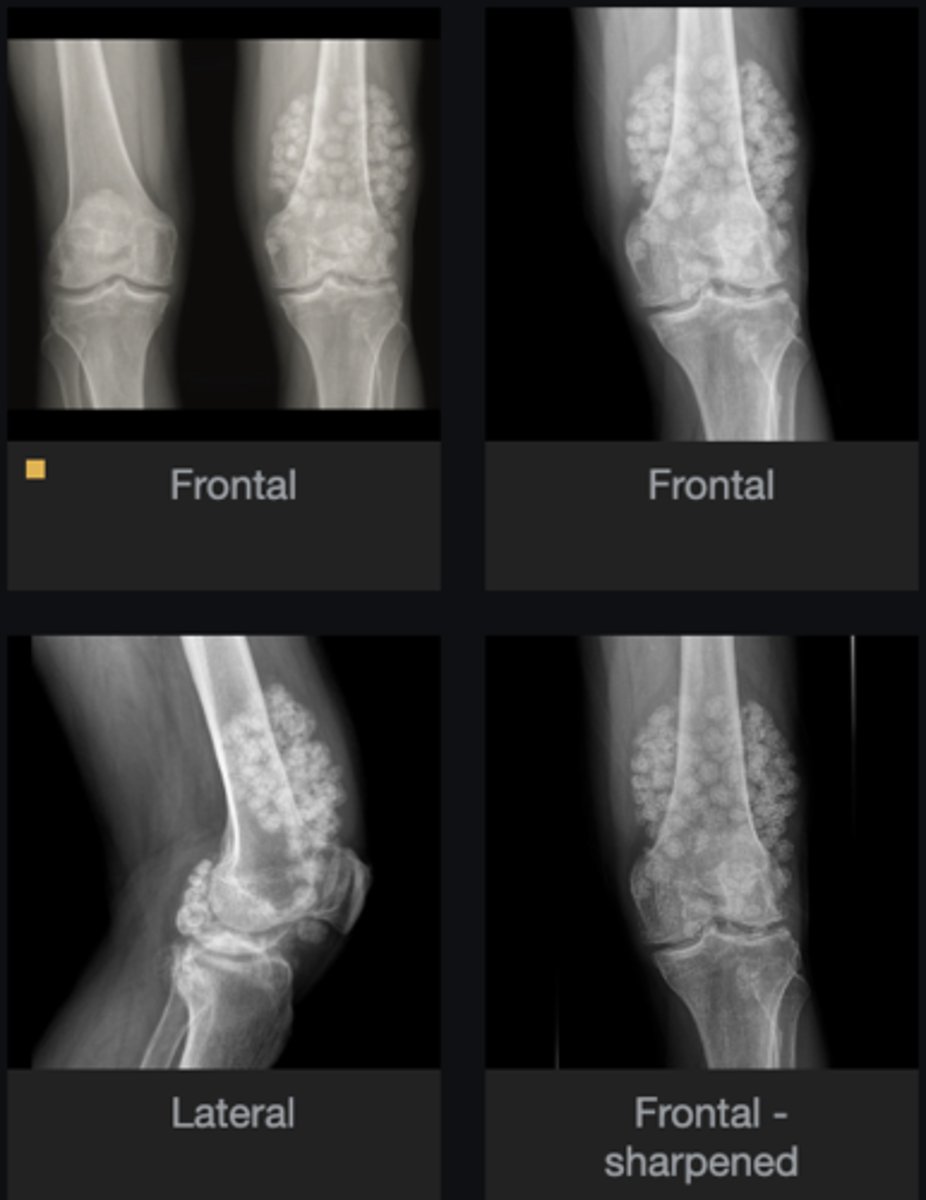

- Subluxation

- Non-uniform loss of joint space (medial tibiofemoral joint)

- Osteophytes

- Subchondral sclerosis

Describe findings

Osteoarthrosis

Diagnosis?

Genu varum

Clinically, the patient's lower extremities would take on what kind of appearance?

Patellar tooth sign

How would you describe the anterior aspect of the patella and what does it indicate?

- Intra-articular calcifications

- Loose bodies

List main findings

- Unilateral loss of joint space

Any secondary findings?

Synoviochondrometaplasia (SCM)

Orthopedic surgeon referral

Next step?